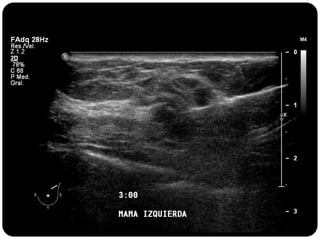

Paciente femenina de 66 años con historia clínica de 1er gesta antes de los 30 años y antecedentes de lactancia positiva, presenta una lesión palpable en la mama derecha. Los estudios radiológicos indican un diagnóstico de bi-rads 5, con biopsias revelando adenocarcinoma lobulillar infiltrante en la glándula mamaria derecha y adenocarcinoma ductal in situ en la izquierda. El caso fue evaluado por las doctoras Jacqueline Preciado Vargas y Beatriz E. González Ulloa.